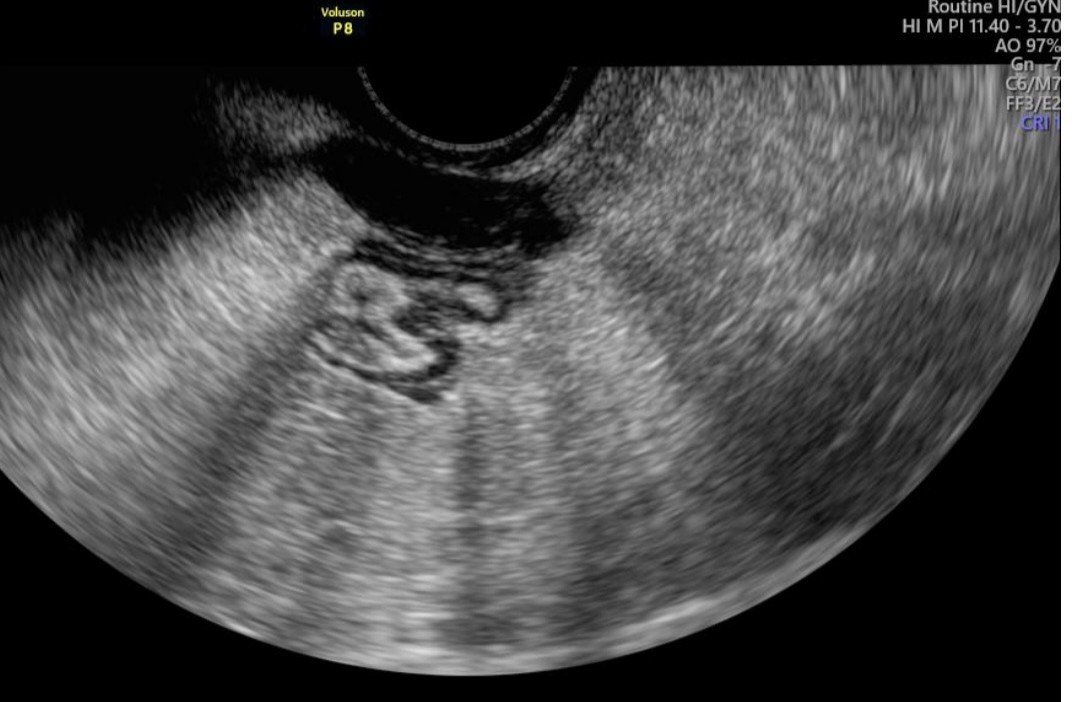

Семира, как я прави тази МБ биопсия? Аз сега пуснах Фемофлор и чакам резултати, че имах една БВ, но мисля на следващ цикъл да пусна Фертилити. То ендометриалната биопсия не е ли това, Фертилити? В моята матка няма течност. Док е видяла правоъгълна кистична формация. Ще се опитам да пусна снимка. Иначе преди една седмица пак ходих, но при друг АГ и то беше малко след Ц, когато повече има видимост и той нищо не видя. А миналия месец още 4-ма ме гледаха, те ли са зле, тя ли си измисля, не знам. Има нещо, ама какво е и дали ще го има другия месец, не знам. Факта е че досега никой нищо не е видял, само тя твърди, че е това. И ме праща на ЯМР за малък таз. ( на снимката черното)